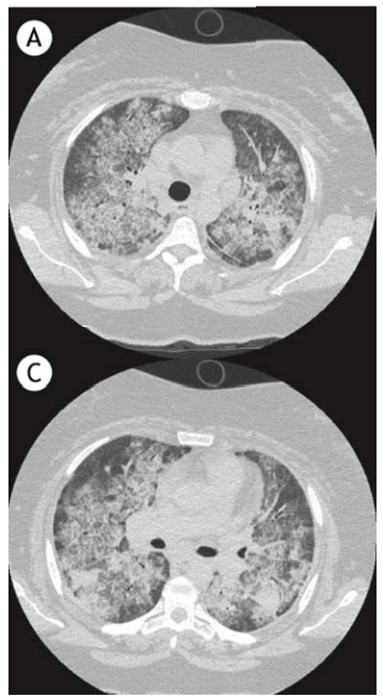

Um homem de 36 anos de idade, cabeleireiro, tabagista (cinco anos/maço), evoluiu progressivamente, durante o último ano, com dispneia e “sensação de afogamento”. Procurou diversos serviços durante esse período, tendo sido diagnosticado com síndrome respiratória gripal por covid duas vezes, devido aos achados tomográficos, porém com sorologia e PCR negativos em ambos os momentos. Realizou, também, testes para tuberculose e pneumocistose, ambos negativos. No momento, sem queixas ao repouso e saturando 94% em ar ambiente.